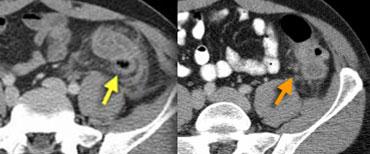

CT điển hình của viêm mấu nối mạc nối với khối mỡ bên phải được bao quanh bởi một vòng tăng tỷ trọng.

Viêm mấu nối mạc nối.

Các mấu nối mạc nối là những phần nhô ra nhỏ chứa mô mỡ từ bề mặt thanh mạc của đại tràng.

Một mấu nối mạc nối có thể bị xoắn và viêm thứ phát gây đau bụng khu trú, bắt chước viêm ruột thừa khi nằm ở hố chậu phải hoặc bắt chước viêm túi thừa khi nằm ở hố chậu trái.

Dấu hiệu vòng đặc trưng tương ứng với lớp phúc mạc tạng bị viêm bao quanh một mấu nối mạc nối bị nhồi máu.

Viêm mấu nối mạc nối bên trái ở bệnh nhân nghi ngờ lâm sàng là viêm túi thừa. Dấu hiệu vòng tăng tỷ trọng đặc trưng.

Dấu hiệu chính: Khối mỡ bị viêm nằm kề cạnh đại tràng với dấu hiệu vòng đặc trưng.